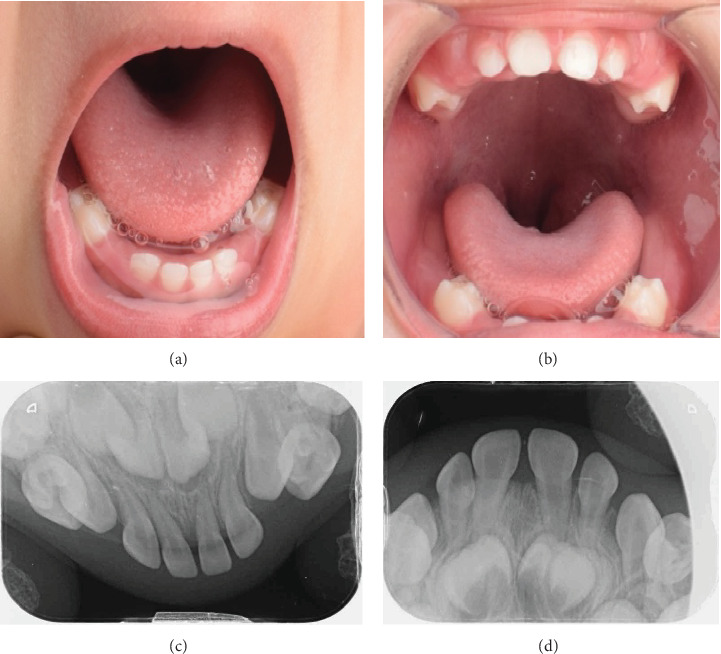

生殖髌骨综合征(GPS)是一种罕见的遗传性疾病,其临床表现包括髌骨缺失、精神运动迟缓、先天性下肢屈曲畸形和泌尿生殖系统异常。一名五岁女童到牙科学院诊所作例行牙科检查。体格检查显示明显的表型特征,特别是宽缩略图和肢体皱纹,而面部外观在正常范围内。出生时,患者表现为畸形畸形的内翻足,生殖器异常,双侧肾积水和肝肿大。随后的MRI评估显示双侧股骨滑车发育不良伴外侧髌股脱位,伴明显的胫骨旋转和垂直距骨。此外,双侧后脚外翻畸形和第一跖趾关节屈曲畸形也被注意到。Sanger测序的分子分析鉴定了KAT6B基因的一个从头杂合无义突变(c.4117, p.Glu1373Ter)。口腔检查显示临床牙冠缩短,乳牙无龋,乳牙(Cs)和第二磨牙(Es)的萌牙延迟。x线评估显示现有的初级e和门牙延迟出牙。本报告阐明了GPS与口腔表现之间的潜在联系,特别强调了原发性Es的延迟爆发。由于缺乏针对该综合征的口腔和牙齿表现的出版物,因此该临床病例有助于诊断,尽管不是具体的。

Genitopatellar syndrome (GPS) is a rare genetic disorder characterized by a spectrum of clinical manifestations including the absence of patellae, psychomotor retardation, congenital flexion deformity of the lower limbs, and genitourinary abnormalities. A 5-year-old female presented to the Faculty of Dentistry Clinic for a routine dental examination. Physical examination revealed distinctive phenotypic features, notably wide thumbnails and limb wrinkling, while facial appearance appeared within normal limits. At birth, the patient exhibited dysmorphic clubfoot, genital anomalies, bilateral hydronephrosis, and hepatomegaly. Subsequent MRI evaluation disclosed bilateral dysplastic femoral trochlea with lateral patellofemoral dislocation, accompanied by marked tibial rotation and vertical talus. Additionally, bilateral hindfoot valgus deformity and first metatarsophalangeal joint flexion deformity were noted. Molecular analysis using Sanger sequencing identified a de novo heterozygous nonsense mutation (c.4117, p.Glu1373Ter) in the KAT6B gene. Oral examination revealed shortened clinical crowns, absence of caries in the primary teeth, and delayed eruption of the primary canines (Cs) and second molars (Es). Radiographic assessment demonstrated existing primary Es and incisors with delayed eruption. This report elucidates a potential association between GPS and oral manifestations, particularly highlighting delayed eruption of primary Es. Since there is a scarcity of publications addressing the oral and dental manifestations of the syndrome, this clinical case contributes, albeit not specifically, to the diagnosis.